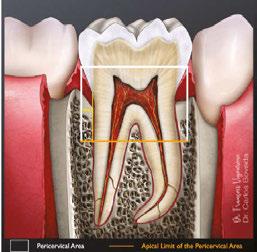

There are various factors that influence the size of such cavities, notably the anatomical location of the orifices and visualizing these orifices without tilting the mirror.12 This results in an access cavity that is widest occlusally and smallest at the level of the orifices.12,13 Hence the drawback of such access cavity design is that it requires the removal of healthy tooth structure, specifically the pericervical dentin — the dentin present 4 mm above and 6 mm below the crestal bone which helps to distribute any forces placed on the tooth (Figure 1).14 This access design, known as Traditional Endodontic Cavity (TEC) is presently being questioned, giving rise to various access designs emphasizing the preservation of this pericervical dentin.14,15

sistence of apical periodontitis. The purpose of an access cavity is to offer the clinician a proper entry into the pulpal chamber, the canal orifices, and into the canals all the way to the working length. It should allow the easy way-in and way-out of all the mechanical and chemical armamentarium during a root canal treatment.11

Traditionally, the endodontic access cavity was designed in a way that aimed to remove any obstruction in the way of reaching the canal orifices. This included the complete unroofing of the chamber, exposing all pulp horns, and obtaining a straight-line access to the apex — avoiding the need to alter visual angulation. This design also aimed at reducing the likelihood of iatrogenic errors.